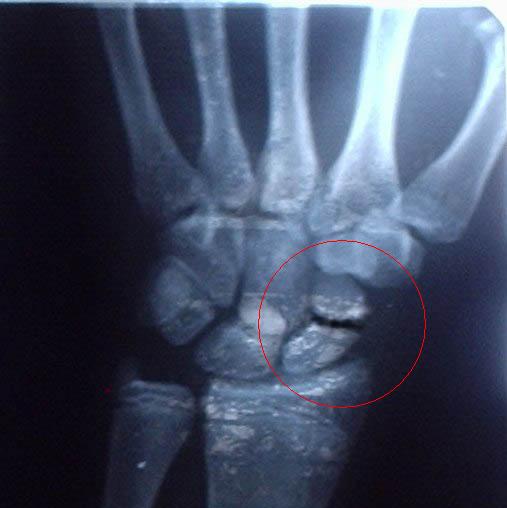

сломана ладьевидная кость 2.04.2005 само не сростается. нужна операция. Так до сих пор и не сделал

Миниатюры

Нажмите на изображение для увеличения

Название: gudron_911_173.jpg

Просмотров: 1769

Размер:	36.8 Кб

ID:	22700